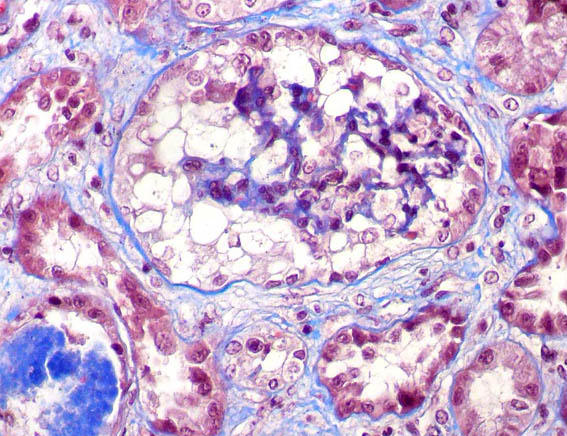

Figure 2. Masson's trichrome, X400.